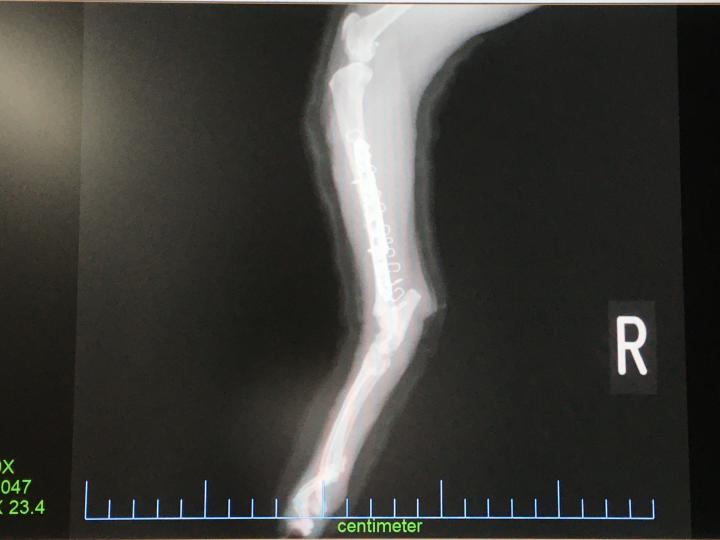

てことで骨折

アフター

猫骨折してプレートいれる手術終わって1週間経過ー。